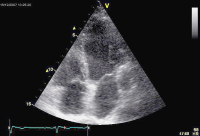

Echokardiographie aktuell: Tubuläre Struktur im Bereich des Sulcus atrioventricularis links bei 2 Patienten

Journal für Kardiologie - Austrian Journal of Cardiology 2009; 16 (1-2): 46-47 Volltext (PDF) Abbildungen mit Filmsequenzen